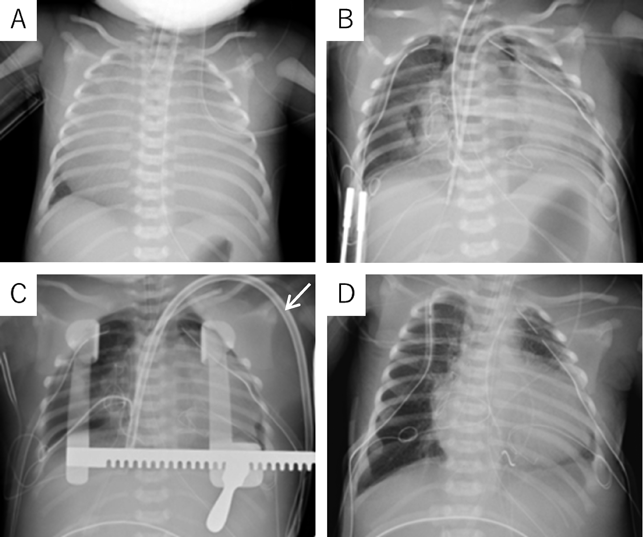

At 37 weeks 5 days’ gestation, a 2,756 g female baby was delivered via elective cesarean section. Artificial ventilation was begun, and prostaglandin was administered. Saturation of percutaneous oxygen (SpO2) increased from 20% to 50%. Apgar scores were 2 and 2 at 1 and 5 minutes after birth, respectively. A chest radiograph showed severe cardiomegaly and a cardiothoracic ratio of 98% (Fig. 2). An echocardiography confirmed the prenatal diagnosis and showed massive tricuspid regurgitation. She continued to be hypoxic with SpO2 at 50% after intubation. Within 92 minutes after birth, surgery was initiated using cardiopulmonary bypass with an arterial cannula into the ascending aorta and bi-caval venous cannulae. The ductus arteriosus was ligated, and the tricuspid valve annulus was closed using a 0.4 mm expanded polytetrafluoroethylene patch with a 3 mm-diameter hole. The atrial septum and the dilated right atrial wall were excised widely. After aortic unclamping, the right ventricular wall was plicated longitudinally using 3-0 braids (Nespolene®, Alfresa, Osaka, Japan). An aorto-pulmonary shunt was constructed, using a 3.0 mm-diameter expanded polytetrafluoroethylene tube graft, between the brachiocephalic artery and the right pulmonary artery. During weaning from cardiopulmonary bypass, hypoxia and hypoventilation were observed. Therefore, HFV (fraction of inspired oxygen (FiO2), 100%) with inhaled nitric oxide (iNO) 20 ppm was used to successfully wean from cardiopulmonary bypass. The patient was returned to the intensive care unit with her chest open.

Fig. 2 Chest radiographs. (A) Immediately after birth. (B) After right ventricular exclusion procedure. (C) After introduction of VV ECMO. A white arrow shows 13 Fr blood access catheter. (D) After chest closure.

On the postoperative day 3, severe hypoxia suddenly developed (SpO2 decreased from 82% to less than 50%), followed by hypotension. An echocardiogram detected smooth flow across the aortopulmonary shunt and good left ventricular function. Therefore, we determined that the cause of hypoxia was due to pulmonary insufficiency, not because of an issue related to pulmonary blood flow. We decided to utilize VV ECMO. A 13 Fr double-lumen blood access catheter (Power Trialysis®, Becton Dickinson Inc., NJ, USA) was inserted from the right atrial appendage to the inferior cava vein. Venous blood was withdrawn from the tip of the catheter, and oxygenated blood was sent back into the atrium (Fig. 3A). VV ECMO (50 mL/kg/min, FiO2 100%) was initiated. Hemodynamics improved dramatically and stabilized. We performed systemic heparinization to maintain an Activated Clotting Time of 200 to 250 seconds during VV ECMO. HFV, minimal catecholamine support (dopamine: 2 µg/kg/min), and surfactant therapy were administered. We performed lung recruitment every day and reduced iNO from 20 to 1 ppm. After 7 days on ECMO, the lung fields on the chest radiograph improved and the ECMO flow was gradually decreased to the flow of 20 mL/kg/min with FiO2 30%. On postoperative day 12, VV ECMO was separated (Fig. 3B). The patient was weaned from iNO on the postoperative day 13 and had her chest closed on the postoperative day 24 with no problems in cardiac and lung function. She was discharged on postoperative day 106 (SpO2 90% in room air). The non-fenestrated Fontan circulation was established two years and nine months following the bidirectional Glenn procedure. Preoperative catheterization before the Fontan procedure showed pulmonary artery index of 215 mm2/m2 and pulmonary vascular resistance of 1.6 U·m2. The six-year-old has normal activity without a neurological deficit.